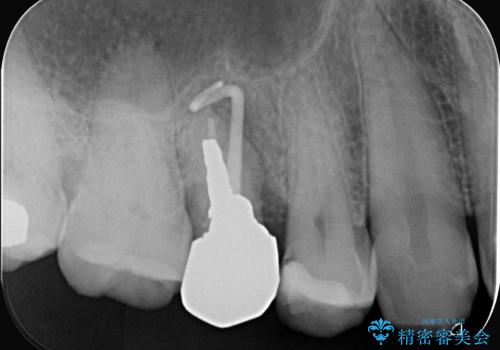

右上5番が根尖性歯周炎と歯周病が同時に併発しており、骨が大きく溶け、歯の動揺も著しかったため保存困難と判断をし抜歯してインプラントで治療を行いました。

インプラントはインプラント周囲炎になりにくいスクリュータイプを使用しています。

インプラントと骨が強度にくっつくように骨密度を上げながらドリリングを行っているのと、患者様の骨の状態に合わせてインプラントの形態を選ぶことで可能となっています。